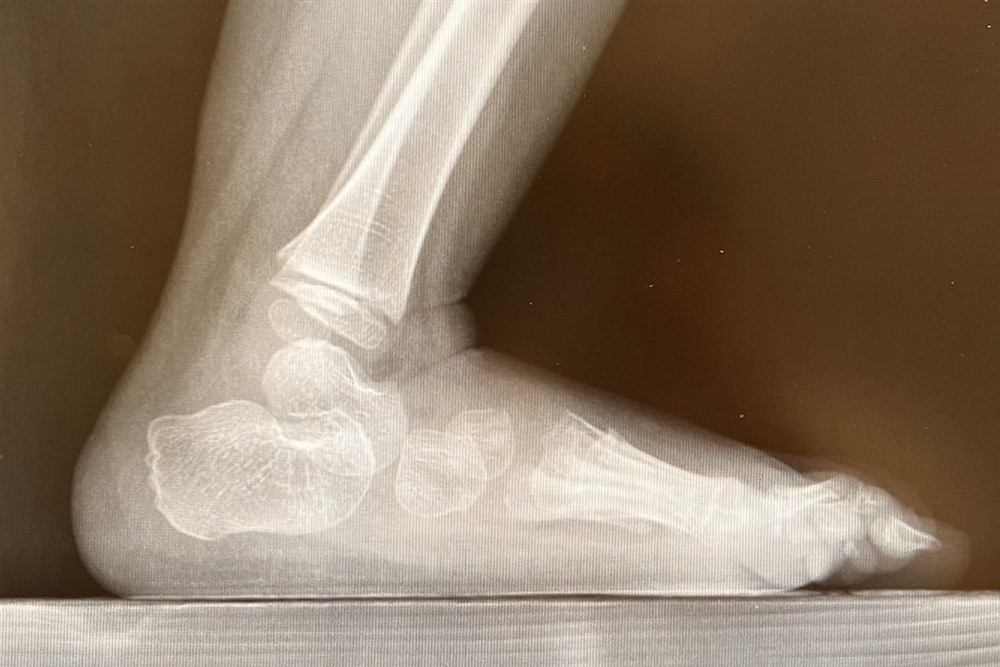

部分脊柱裂孩子的足弓特別高及內翻,是由脛骨後肌和腓骨肌之間的肌肉不平衡以及內在肌無力引起的。圖/台北慈濟醫院

邱佳儀醫師說,軒軒從出生開始腳的肌肉就沒有力氣,會因為肌力不平衡而導致關節變形,再加上感覺功能的缺損,皮膚容易磨損、長繭,因此會讓他穿上特殊鞋墊,防止足部肌肉關節的變形。

邱醫師一邊評估,一邊請軒軒站起來走一小段路,審視他的走路步態。接著,邱醫師告訴爸爸:「因為病灶的部位影響到足部,會有足弓塌陷及腳趾像爪子般彎曲的現象,我們等等會重新替軒軒製作新的鞋墊,才不會影響腳的變形與行走的步態。」